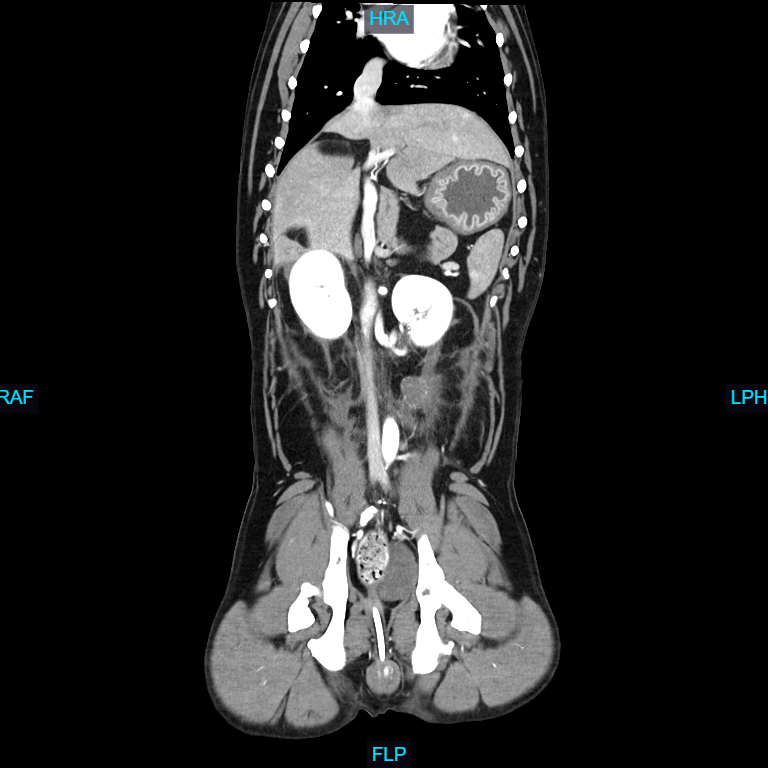

Computed Tomography (CT), also known as a CAT scan, is an advanced imaging technique that combines X-ray technology with computer processing to generate detailed cross-sectional images of an animal's internal structures.

The animal is typically sedated or anesthetized to remain still during the procedure, ensuring high-quality images. Special positioning aids may be used to maintain the correct posture. The animal is placed on a motorized table that moves through a circular opening of the CT scanner. The scanner consists of an X-ray tube that rotates around the animal, emitting X-rays from different angles. Veterinarians and veterinary radiologists analyze the CT images to identify abnormalities such as tumors, fractures, organ diseases, and other conditions. The high-resolution images allow for a detailed examination that is often not possible with traditional X-rays.

- Assessing organs like the liver, kidneys, lungs, and intestines for diseases, obstructions,

and other abnormalities.